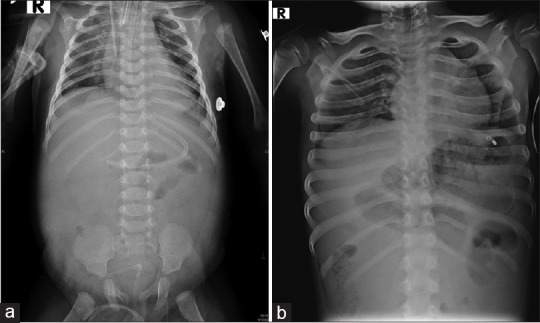

摘要:跨中心疝是内疝的一种,肠环通过肠系膜缺损疝出。这种疝的症状多种多样,但没有任何特殊的放射学特征,导致诊断延误和高死亡率。在这里,我们介绍了四例这种罕见但致命的小肠梗阻患者的系列病例。三名患儿因小肠梗阻就诊于急诊科。另一名患儿是早产新生儿,产前扫描显示为小肠梗阻。所有患儿都接受了急诊开腹手术,结果发现肠系膜缺损,小肠疝出和坏疽。医生对坏疽肠段进行了切除吻合,并缝合了肠系膜缺损。儿童小肠梗阻的鉴别诊断应包括跨中心疝。实验室或影像学检查往往无法得出结论。在这种罕见但危及生命的情况下,及时进行手术可以挽救生命。

Abstract: Transmesentric hernias are a type of internal hernia, in which there is herniation of bowel loops through a defect in the mesentery. They present with a wide variety of symptoms without any specific radiological features, leading to a delay in diagnosis and high mortality rate. Here, we present a case series of four patients with this rare but fatal cause of small bowel obstruction. Three children presented to the emergency department with small bowel obstruction. The other baby was a preterm neonate with an antenatal scan showing small bowel obstruction. All children underwent emergency laparotomy and were found to have a mesenteric defect with herniation and gangrene of the small bowel. Resection anastomosis of the gangrenous segment and closure of the mesenteric defect were done. The differential for small bowel obstruction in children should include transmesentric hernia. Laboratory or imaging investigations are often inconclusive. Timely exploration can save lives in this rare but life-threatening condition.